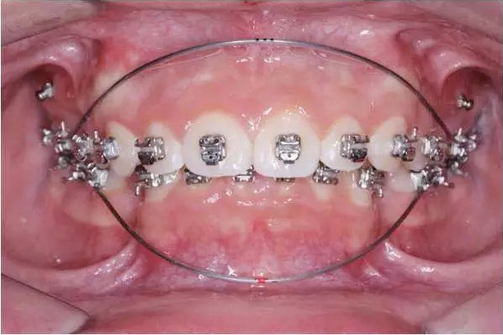

矯治過程中的第二組弓絲可以直接選擇高彈性的熱激活鎳鈦方絲。對(duì)于主動(dòng)式自鎖托槽,一般選擇0.016 ×0.022英寸的熱激活鎳鈦方絲,對(duì)于被動(dòng)式自鎖托槽,一般選擇0.014 ×0.025英寸或者0.016×0.025英寸的熱激活鎳鈦方絲,弓絲的頰舌徑尺寸與槽溝的深度之間差距很小,這樣可以盡可能減小弓絲與槽溝間的余隙,有利于牙齒扭轉(zhuǎn)的快速矯正(圖2)。第三組弓絲一般選擇0.019 ×0.025英寸的熱激活鎳鈦方絲,繼續(xù)排齊整平上下牙列,為矯治第二階段采用硬度大的不銹鋼工作弓絲做好充分準(zhǔn)備。

圖2 減小弓絲與溝槽間的余隙有利于扭轉(zhuǎn)的快速矯正